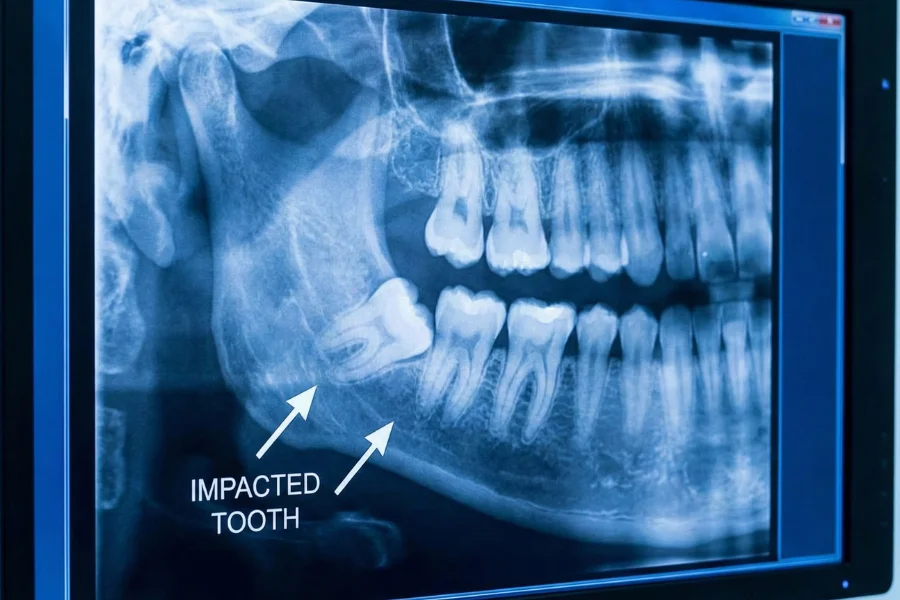

Impacted teeth are teeth that do not emerge fully into the mouth due to lack of space, improper position, or obstruction by other teeth or bone. Wisdom teeth are the most commonly impacted, but other teeth can also be affected. If left untreated, impacted teeth can lead to pain, infection, and damage to nearby teeth.

Damage to adjacent teeth seen on X-rays

Clinical examination and X-rays

Assessment of tooth position

Wisdom teeth are the most commonly impacted teeth.